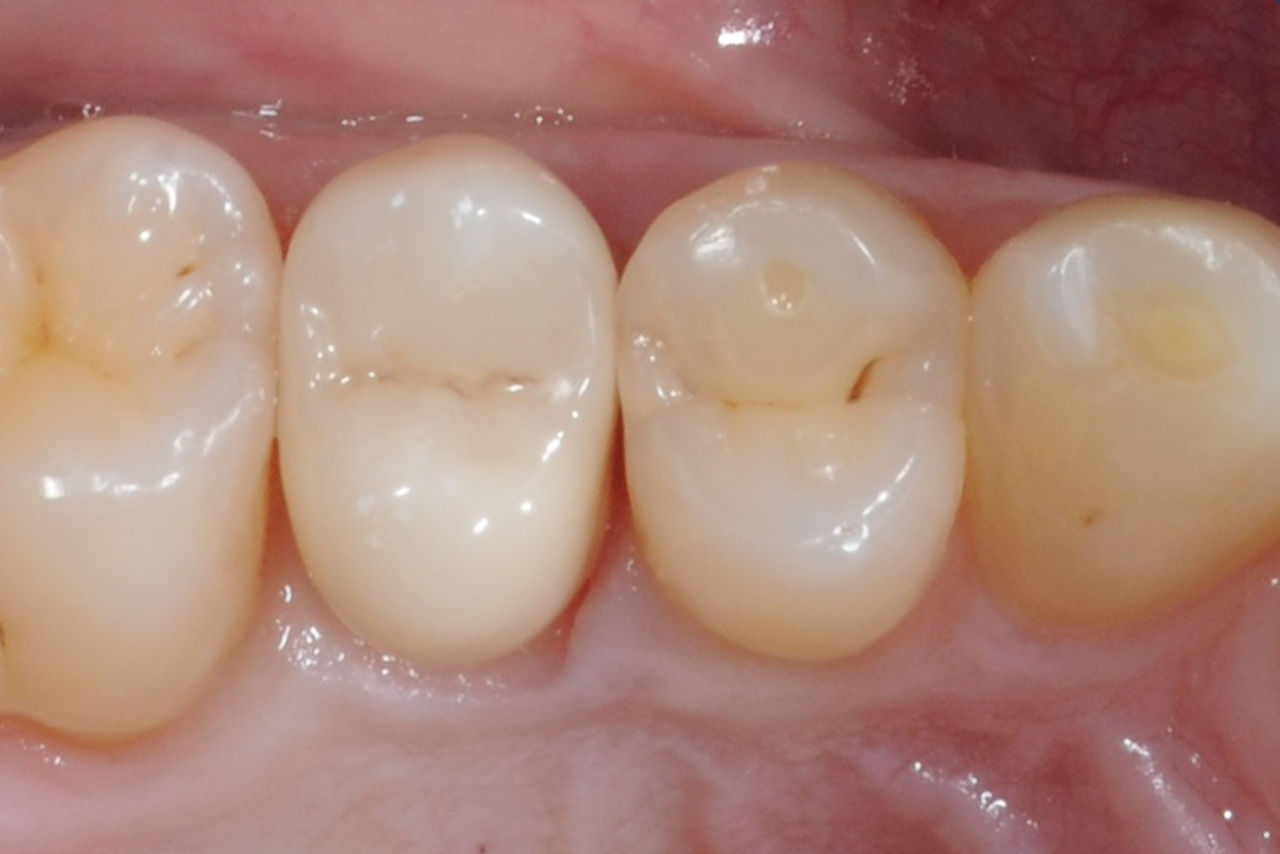

Before: Tooth 26 presenting decay and a failing direct composite restoration.

After: Highly esthetic and functional lithium disilicate ceramic crown.